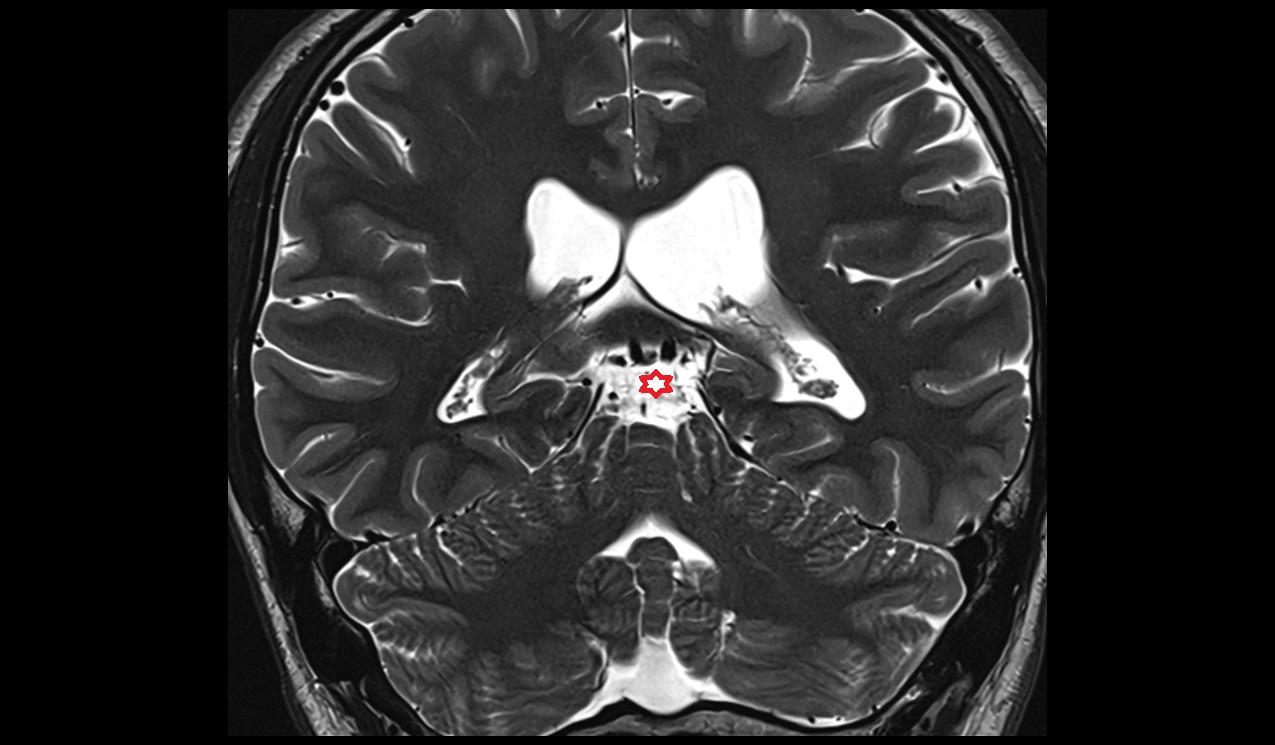

- Interpeduncular Cistern

- Fourth ventricle

- Median aperture of fourth ventricle (foramen of Magendie)

- Median sulcus of rhomboid fossa